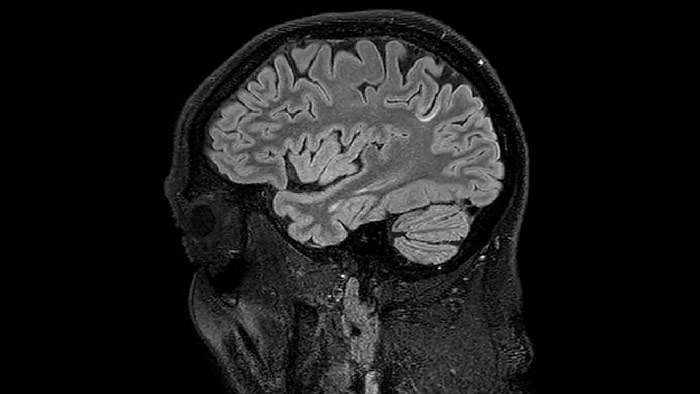

Juxtacortical MS lesion elition

Sagittal 3D FLAIR with 0.3 mm3 voxel volume acquired in 5:12 min. using Compressed SENSE showing a (juxta)cortical MS lesion.